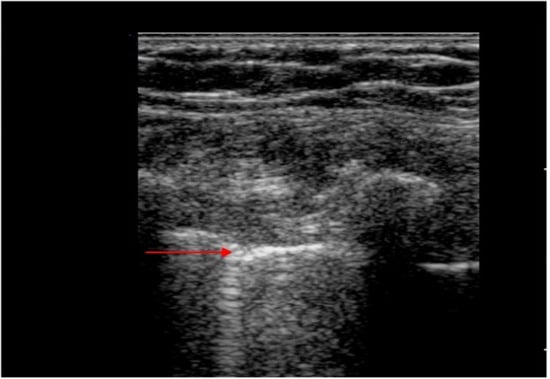

Pneumothorax

Patterns in the LUS Examination